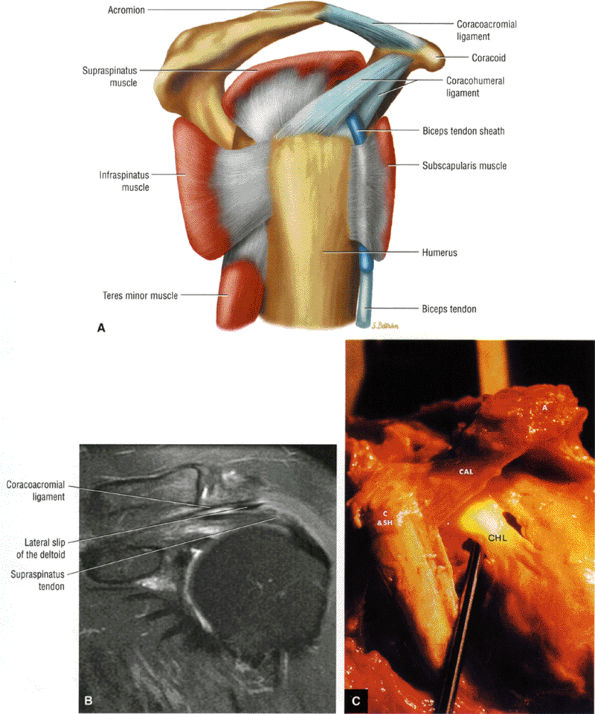

FIGURE 8.101 ● (A) The coracoacromial ligament extends from the inferior surface of the acromion to the lateral aspect of the coracoid. The humeroscapular motion interface represents a relationship between the rotator cuff, the humeral head, the biceps, the coracoacromial arch, and the deltoid and the coracoid muscles. Contact and load transfer occur between the rotator cuff and coracoacromial arch. (B) Coronal FS PD FSE image demonstrates the course of the coracoacromial ligament to the undersurface of the acromion. The lateral slip of the deltoid extends between the coracoacromial ligament and the rotator cuff. (C) Gross specimen highlighting the anatomy of the coracohumeral ligament (CHL) and coracoacromial ligament (CAL). The coracobrachialis (C), the short head of the biceps (SH), and the acromion (A) are indicated.